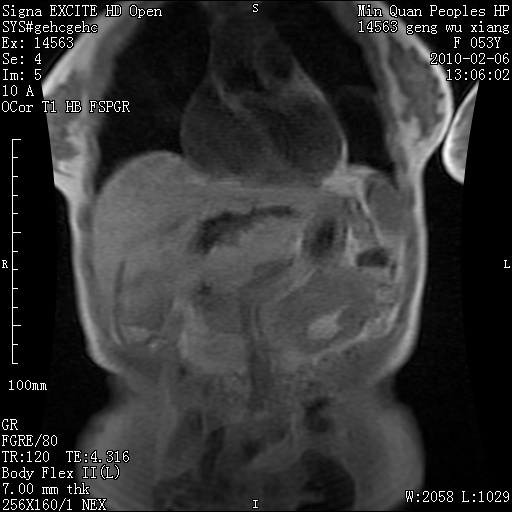

标题: MRI2762:胆道梗阻原因?

f,53y,全身黄染多日。

高位胆道梗阻 胆管癌可能性大

支持 高位胆道梗阻 胆管癌可能性大。